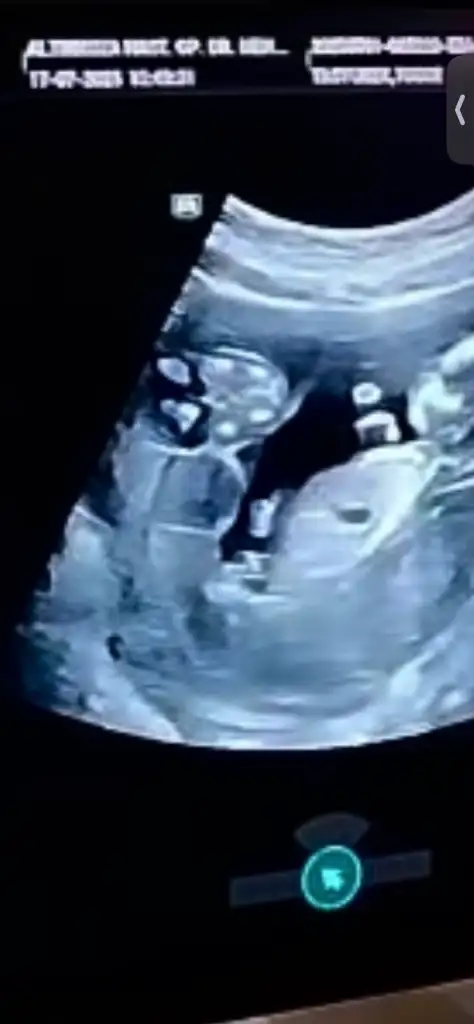

Kızlar bunda bakarmısınız üsteki bebeğe doktor erkek olabilir ama üstünden kordon geçiyor dedi anlık bir görüntü yakaladı onun dışında kendini kapattı cinsiyet nedir sizce böyle kordon olabilirmi üsteki ip gibi geçen şey bence kordon

Eklentiler

• IMG_3482.webp

13,5 KB · Görüntüleme: 30